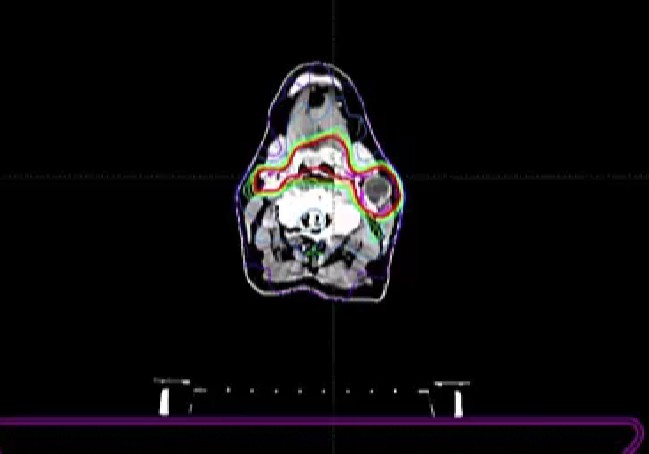

dosimetry, ipsilateral radiotherapy, randomized study, bilateral radiotherapy, cisplatin, linac, linear accelerator, Armenia, toxicity, neutropenia, gastrostomy, odynophagia, dysphasia, dehydration, anemia, blood transfusion, kidney function, SIB, symmetrical boost, sequential boost, contouring, ...

Elective Neck dose, Reirradiation, Carotid artery dose, 40Gy to neck, Pentoxyfylline and Vitamin E for neck Fibrosis, Neck failure rates, Submandibular Gland sparing, Review Dr. Sher’s plan, tongue tumor, dose versus volume, contralateral failure, oropharynx, drug trials, nasopharynx, volume desi...